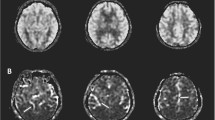

Using ASL-MRI, PLD1.5 scans revealed significant positive correlations with MMSE results in the right posterior cingulate cortex (PCC) and both temporo-parietal association cortexes, in addition to the right rectal gyrus (Fig 1a). PLD2.5 showed significant positive correlations in the superior parietal lobule but not PCC, and the right temporo-parietal association cortex only. Positive correlations for the right inferior temporal lobule and right fusiform gyrus were also significant (Fig 2a). Brain perfusion SPECT identified significant positive correlations in the PCC and both temporo-parietal association cortexes (right-side dominant), and the left fusiform gyrus (Fig 3a). The plots of the correlation between the voxel values and MMSE scores at the most significant area are shown in Figs. 1b, 2b, and 3b. All of them showed linear relationships. The expected voxels per cluster for PLD1.5, PLD2.5, and SPECT were 63.4, 40.8, and 60.9, respectively. Cluster-level statistics for all rendered clusters are summarized in Table 2.

Voxel-wise differences in CBF between PLD1.5 and PLD2.5

PLD1.5 showed significantly higher CBF than PLD2.5 at the proximal areas of vascular territories of the anterior, middle, and posterior cerebral arteries (Fig 4).

From the results of our study, we identified significant positive correlations between CBF and cognition, when measuring using both ASL-MRI and SPECT. The main areas with significant results were located in PCC and temporo-parietal association cortexes, which are known to show decreases in perfusion or metabolism during cognitive decline in association with AD [25,26,27,28]. These areas are the posterior parts of the default mode network (DMN), which has a primary network center in the PCC. These regions have a strong functional connection to the left and right inferior parietal lobule (IPL), ventral and dorsal medial prefrontal cortex, and lateral temporal lobes [29]. Functional MRI studies have also consistently implicated the DMN as the most vulnerable network in AD [30, 31]. The posterior (temporo-parietal-predominant) DMN may be particularly susceptible in early-stage AD [32–34]. These studies therefore support our findings that a significant correlation exists between CBF and cognition, in the PCC and IPL. To the best of our knowledge, ours is the first report that succeeded in demonstrating such correlations between CBF and cognition using ASL-MRI, with supporting data using SPECT. These correlations may support the idea that regional CBF can serve as a biomarker of the neural changes underlying cognitive decline. As shown in Figs. 1b and 2b, the voxel values of SPM results dropped linearly with decreasing MMSE scores. Our results also showed similar significant correlations between cognition and CBF using ASL-MRI with PLD1.5 and PLD2.5, and SPECT. The measurement of CBF is thought to be influenced by modalities, tracers, and parameters. In fact, our results showed that ASL-MRI with PLD1.5 and PLD2.5 have significant differences. A significantly higher CBF was found at the adjacent areas of anterior cerebral arteries, middle cerebral arteries and posterior cerebral arteries for PLD1.5 compared to PLD2.5, suggesting early perfused areas. Liu et al. [35] evaluated the CBF of AD patients using ASL-MRI with PLD1.5 and PLD2.5, and identified lower CBF for both PLD durations at the specific area of AD pathology when compared to healthy control subjects, but with smaller clusters of voxel for PLD2.5. Despite of these significant differences in measured CBF using ASL-MRI with PLD1.5 and PLD2.5, PCC and temporo-parietal association cortexes were detected with significant correlations with cognition. This may suggest a possibility of the usefulness for the individual diagnosis using voxel-wise analyses of ASL-MRI. In Japan, voxel-wise analyses of SPECT using 3-Dimensional stereotactic surface projections (3D–SSP) [36] and an SPM-based method termed “easy Z-score imaging system (eZIS)” [37, 38] have been commonly used for the individual diagnoses in daily practices. Such voxel-wise methods may be helpful for making individual diagnoses using ASL-MRI. However, an age-specific normal database is required for the detection of significant abnormalities of individual images.